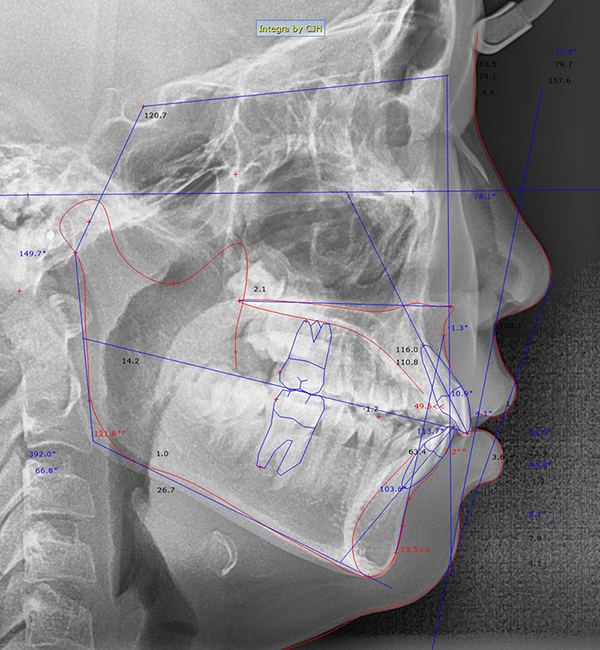

측모, 정면 및 수완부(손) 엑스레이 및 CT 촬영

처음에 먼저 찍었던 파노라마 엑스레이 촬영 이외에 옆 얼굴의 엑스레이 촬영도 합니다. 이러한 옆얼굴 엑스레이는 V ceph 이라고 하는 분석 프로그램을 통해 옆 얼굴의 골격과 연조직의 계측점을 측정하여 골격 형태를 분석하는데 사용됩니다.

제가 수련받을 때는 하나하나 계측점을 손으로 클릭하고 선도 직접 그려서 얼굴뼈와 연조직의 형태를 따라 그리는 트레이싱 이라는 작업을 했는데, 요즘에는 auto tracing 이라는 기능이 생겨서 클릭만 하면 바로 트레이싱이 되어 빠르게 분석을 할 수 있습니다. 예전보다는 자동으로 그리는 기능의 정확도가 훨씬 높아지긴 했지만, 아무래도 몇 개 계측점 정도는 손으로 수정해주는 작업이 (굳이 안해도 되지만 성격상 저는) 필요하긴 합니다 :)

측모 엑스레이 분석 결과 아래와 같은 결과들이 나오게 되는데, 이를 통해 골격의 형태와 치아의 위치관계 등을 알 수 있습니다.

측모 엑스레이 결과